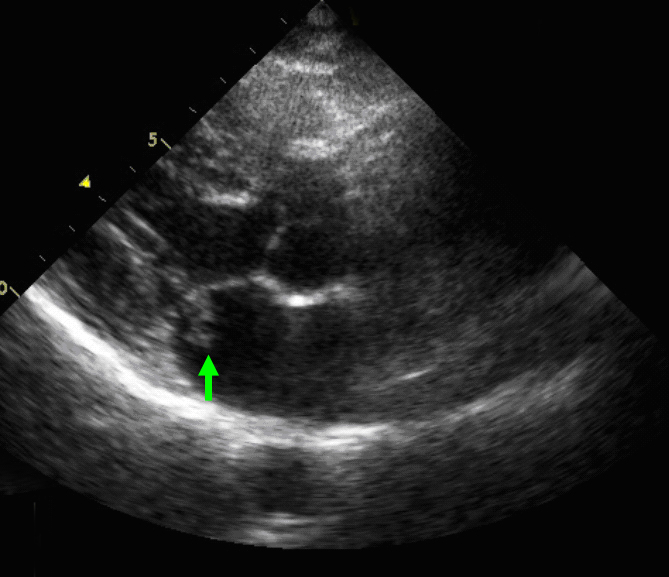

Article "特徴的な心エコー図所見が診断に有用であったレフレル心内膜心筋炎の症例" Detailed information of the J-GLOBAL is an information service managed by the Japan Science and Technology Agency (hereinafter referred to as "JST"). It provides free access to secondary information on researchers, articles, patents, etc., in science and technology, medicine and.. 好酸球増多性心内膜心筋炎. 一いわゆるL6ffler心内膜炎一の1男児例. (平成6年4月26日受付) (平成6年11月28日受理) 1}群馬県立小児医療センター循環器科,現 群馬大学医学部小児科 2)群馬県立小児医療センター循環器科,3)深谷赤十字病院小児科. 小林.

心エコー図検査にて長期間経過観察し得たレフレル心内膜炎の1例

感染性心内膜炎はこんな病気. 感染性心内膜炎とは、「溶血性連鎖球菌 (ようけつせいれんさきゅうきん)」や「ブドウ球菌」、「腸球菌 (ちょうきゅうきん)」、「真菌 (しんきん)」などの菌が、なんらかの原因で血液中に侵入し、心臓内部に感染巣が形成さ.. Article "レフレル心内膜炎および好酸球性心筋炎の発症予測と早期発見方法に関する検討" Detailed information of the J-GLOBAL is an information service managed by the Japan Science and Technology Agency (hereinafter referred to as "JST"). It provides free access to secondary information on researchers, articles, patents, etc., in science and technology, medicine.